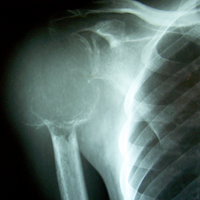

Case:7 GCT Humerus

Spine Surgeon Best In Rajasthan

Pre-Op

Sports Injuries Doctor

3 Years follow-up

Orthopedic Oncology Doctor In Ahmedabad

5 Years follow-up